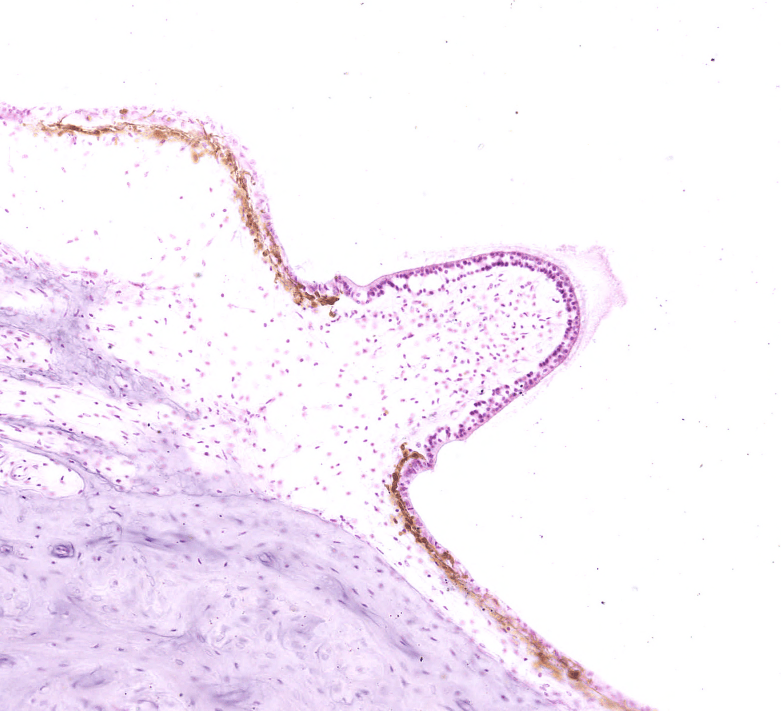

ÓRGANO DE CORTI

Es considerado el epitelio sensitivo de la cóclea, se encarga de procesar los estímulos auditivos.

Órgano de Corti, HyE. Recuperada de la Universidad de Yale.